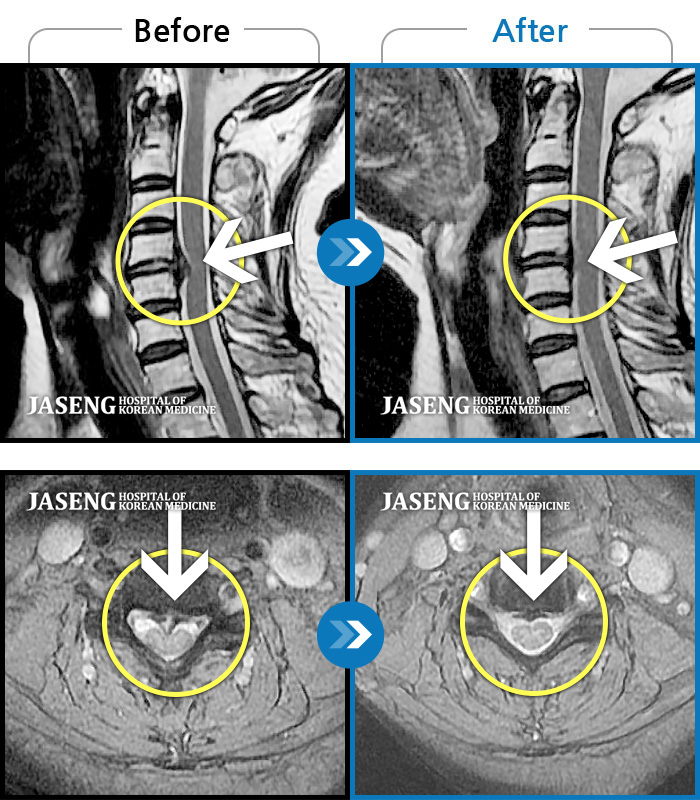

[뱸] 19.11.28~25.05.06